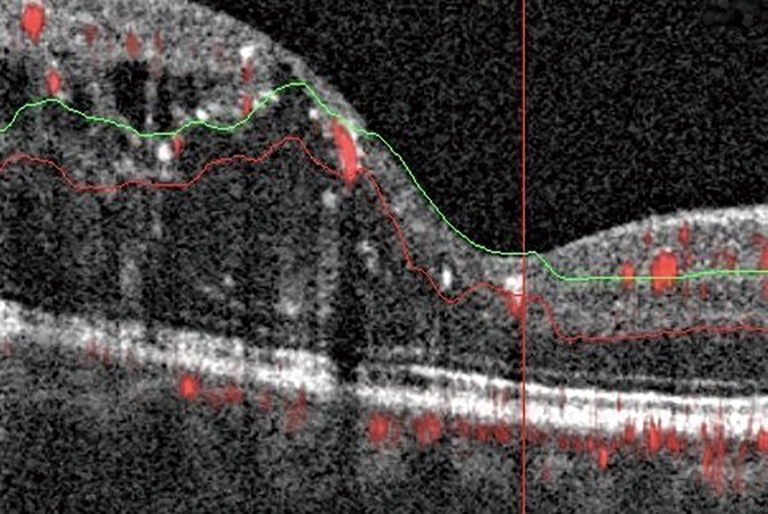

DME develops due to a combination of both VEGF-mediated and inflammatory factors, resulting in alterations in the blood-retinal barrier. The subsequent presence of fluid on OCT may interfere with imaging and segmentation capabilities. This occurs because of difficult automated identification of anatomical landmarks needed for correct segmentation (Figure 3) (20). Incorrect segmentation may affect OCTA images. DME has also been correlated with decreased OCTA signal intensity (9) as the cystoid spaces in DME often attenuate the reflected signal from deeper layers (21). Areas of DME may appear as flow voids on OCTA, areas that lack flow signal. It has been reported that these flow voids on OCTA were frequently larger than the cystoid spaces themselves, giving an inaccurate representation of actual morphology (Figure 4) (22). Studies have also determined the density of microaneurysms in superficial and deep retinal layers. Microaneurysms were found to be more frequent in the deep layer as compared to the superficial layer in eyes with DR. Their density in the deep layer further increases in eyes with DME. Additionally, a correlation between macular volume and the density of microaneurysms in the deep plexus has been demonstrated (23).

figure3

figure4